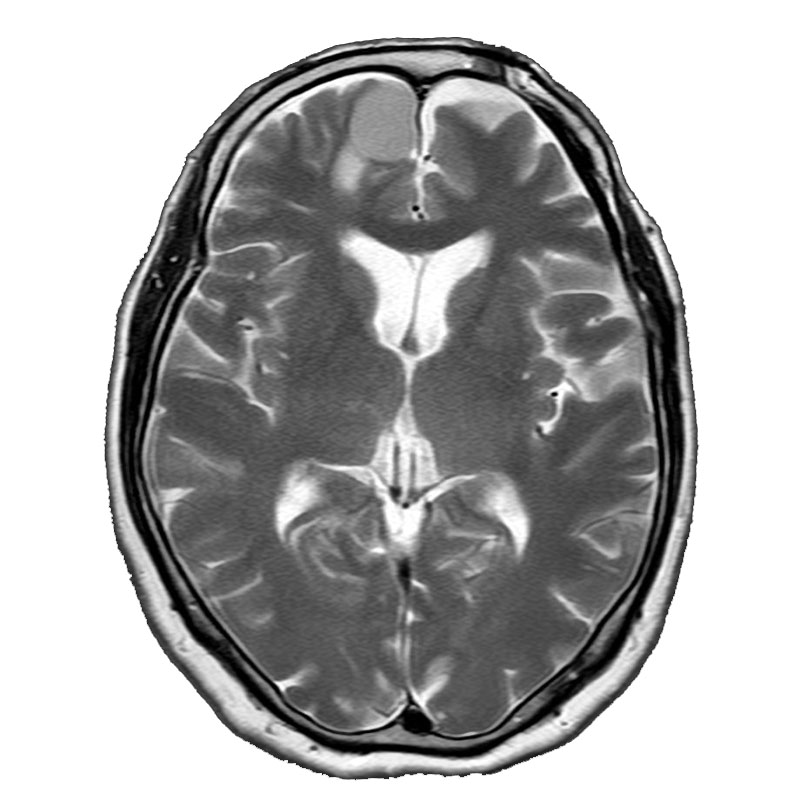

脳動静脈奇形

摘出術

南田/野本/元永